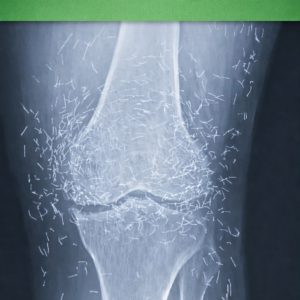

Doctors Discover Unexpected “Gold Mine” in Woman’s Knees

When a 65-year-old woman in South Korea visited doctors for chronic knee pain, they discovered something unexpected — dozens of tiny gold acupuncture needles embedded around her…